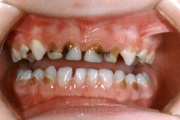

Amelogenesis Imperfecta

Hamba atritsioon

kaaries igemeäärel

kaaries